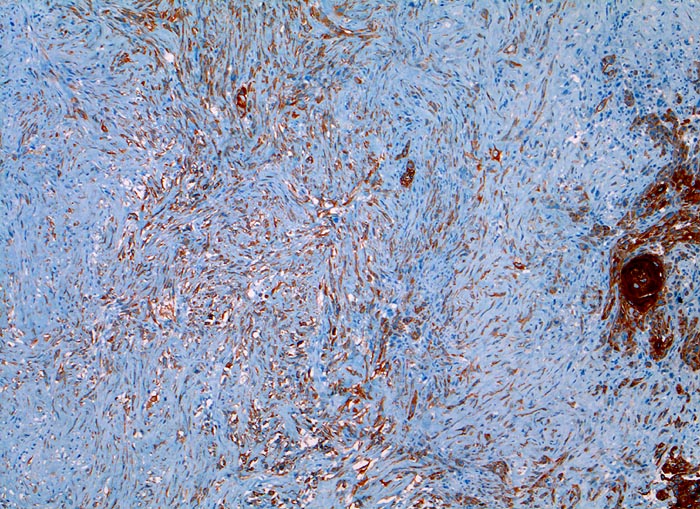

PathoPic – image database / PathoPic ID 3301 - sarkomatoides Plattenepithelkarzinom

sarkomatoides Plattenepithelkarzinom

Larynx

Der Panzytokeratinmarker Lu-5 färbt sowohl die plattenepithelial differenzierten verhornenden Tumor-Zellstränge rechts im Bild als auch ein Teil der sarkomatoiden entdifferenzierten Tumorkomponente an.

Tumor subglottisch rechts. Immunhistochemische Resultate: CK22, Lu-5, Vimentin positiv

Immunhistochemie

Lu5 Panzytokeratin